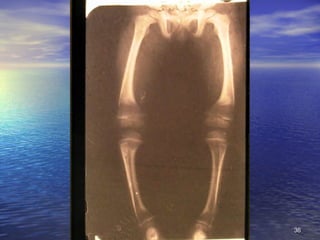

2. Signos Circunstanciales No se encuentran siempre, sino que están condicionados a causas ambientales o ecológicas, no específicas: alteraciones de la piel y faneras, lesiones oculares, de lengua, óseas, de músculos y ligamentos, de aparato digestivo, alteraciones hematológicas, neurológicas, edema

2. Signos CircunstancialesNo se encuentran siempre, sino que están condicionados a causas ambientales o ecológicas, no específicas: alteraciones de la piel y faneras, lesiones oculares, de lengua, óseas, de músculos y ligamentos, de aparato digestivo, alteraciones hematológicas, neurológicas, edema